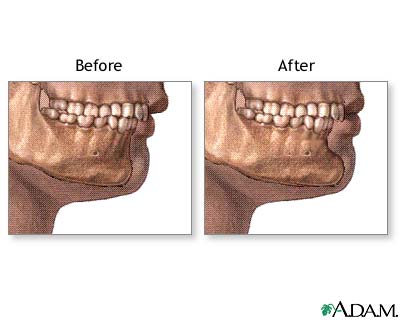

Chin augmentation is mostly done to balance the appearance of the face by making the chin longer or bigger compared to the nose. The best candidates for chin augmentation are people with small or receding chins (microgenia), but who have a normal bite.

You may feel some numbness in your chin for up to 3 months, and a stretching sensation around your chin for 1 week. Most of the swelling will be gone by 6 weeks, depending on the type of procedure you had.

Because you may have some swelling for months, you might not see the final appearance of your chin and jaw for 3 to 4 months.